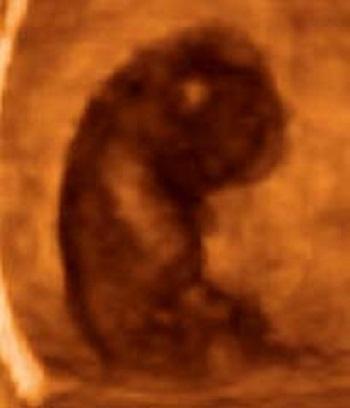

Az a cuki lüktető kis gömbpaca a monitoron a ti babátok! Tényleg a ti babátok? Hát ez él! Milyen kis ügyes! Hogy lüktet! Gyorsan meg kell osztani a hírt mindenkivel. Úgyse bírjátok magatokban tartani. Te felhívod a szüleidet, ő az övéit. Megveszed a gyógyszertárban az összes babavitamint.

12. hét! Szólni kéne a babának is.......Becsapottnak, nyűgösnek, fáradtnak érzed magad. És ekkor apának ötlete támad! Elmentek babamozizni. Igaz, még nem érzed, de a Babócád nagyot nőtt! Mindene van! Mozog, reagál, és mindent érez! Szemetek láttára alszik el. Olyan édes! Órákig el tudnátok nézni. Persze az ultrahangos nőci produkáltatni szeretné a videó miatt, így köhögni kezdesz. A méhedben föltámad a tenger. Babóca felébred, méltatlankodik, majd megnyugszik, oldalára fordul, cumizik és cukin visszaalszik. Hihetetlen! Ettől a pillanattól fogva fáradságtól, rosszulléttől és fájdalomtól függetlenül boldognak, igazán boldognak érzed magad.